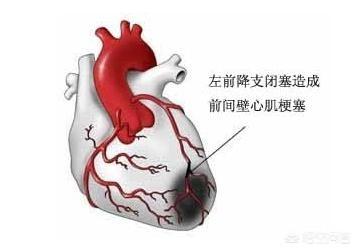

冠状動脈性心臓病は、患者の冠状動脈の血管が何らかの理由で狭窄閉塞し、血液酸素エネルギーの正常な流れに影響を与えるため、胸が締め付けられるような症状を引き起こす可能性があり、患者の日常的な行動が供給よりも多くのエネルギーを消費すると、一連の臨床症状が発生し、胸が締め付けられるような症状は典型的な症状の1つです。

1、冠動脈の急性血栓症と痙攣。冠状動脈性心臓病の大部分の病態生理的基礎は冠状動脈アテローム性動脈硬化症であるが、冠状動脈性心臓病患者の中には冠状動脈のプラークが少ししかなく、狭窄があまり強くなく、狭心症や心筋梗塞さえも冠状動脈内の急性血栓症や冠状動脈の攣縮が原因である。筆者は30代男性の急性梗塞患者に会ったことがあるが、冠動脈の結果はプラークが少ししかなく、冠動脈内の急性血栓と自己溶解が原因であることを考慮した。

2.冠微小血管疾患。冠微小血管疾患(CMVD)とは、様々な病原因子の影響下にある前部小冠動脈および小動脈の構造的および/または機能的異常によって引き起こされる労作性狭心症または心筋虚血の客観的証拠の臨床的症候群を指す。冠動脈には前部小動脈(直径0.1~0.5mm)、細動脈(直径0.1mm未満)、心外膜下冠動脈(直径0.5~5mm)の3つの部分がある。 冠動脈細動脈には前部小動脈と細動脈が含まれ、その構造的・機能的異常も狭心症やその他の臨床症状を引き起こす。

1.心筋ブリッジ:

私は以前、循環器内科のインターンシップでこのような患者に遭遇し、彼は心筋ブリッジと胸の締め付けが原因です。心筋ブリッジは多くの人が理解していないと推定され、ここでこの血管が心臓の内側にある通常の時間を参照するために心臓の表面に長い血管の心臓への血液供給を指し、血管の心臓の表面に長いアーチ型の橋に似ているので、医療専門家はそれを心筋ブリッジの名前を与えるために;心臓の心臓が鼓動するとき心臓が拍動しているとき、この血管が圧迫され、心臓への血液供給が減少するため、胸が締め付けられるような痛みが生じます;